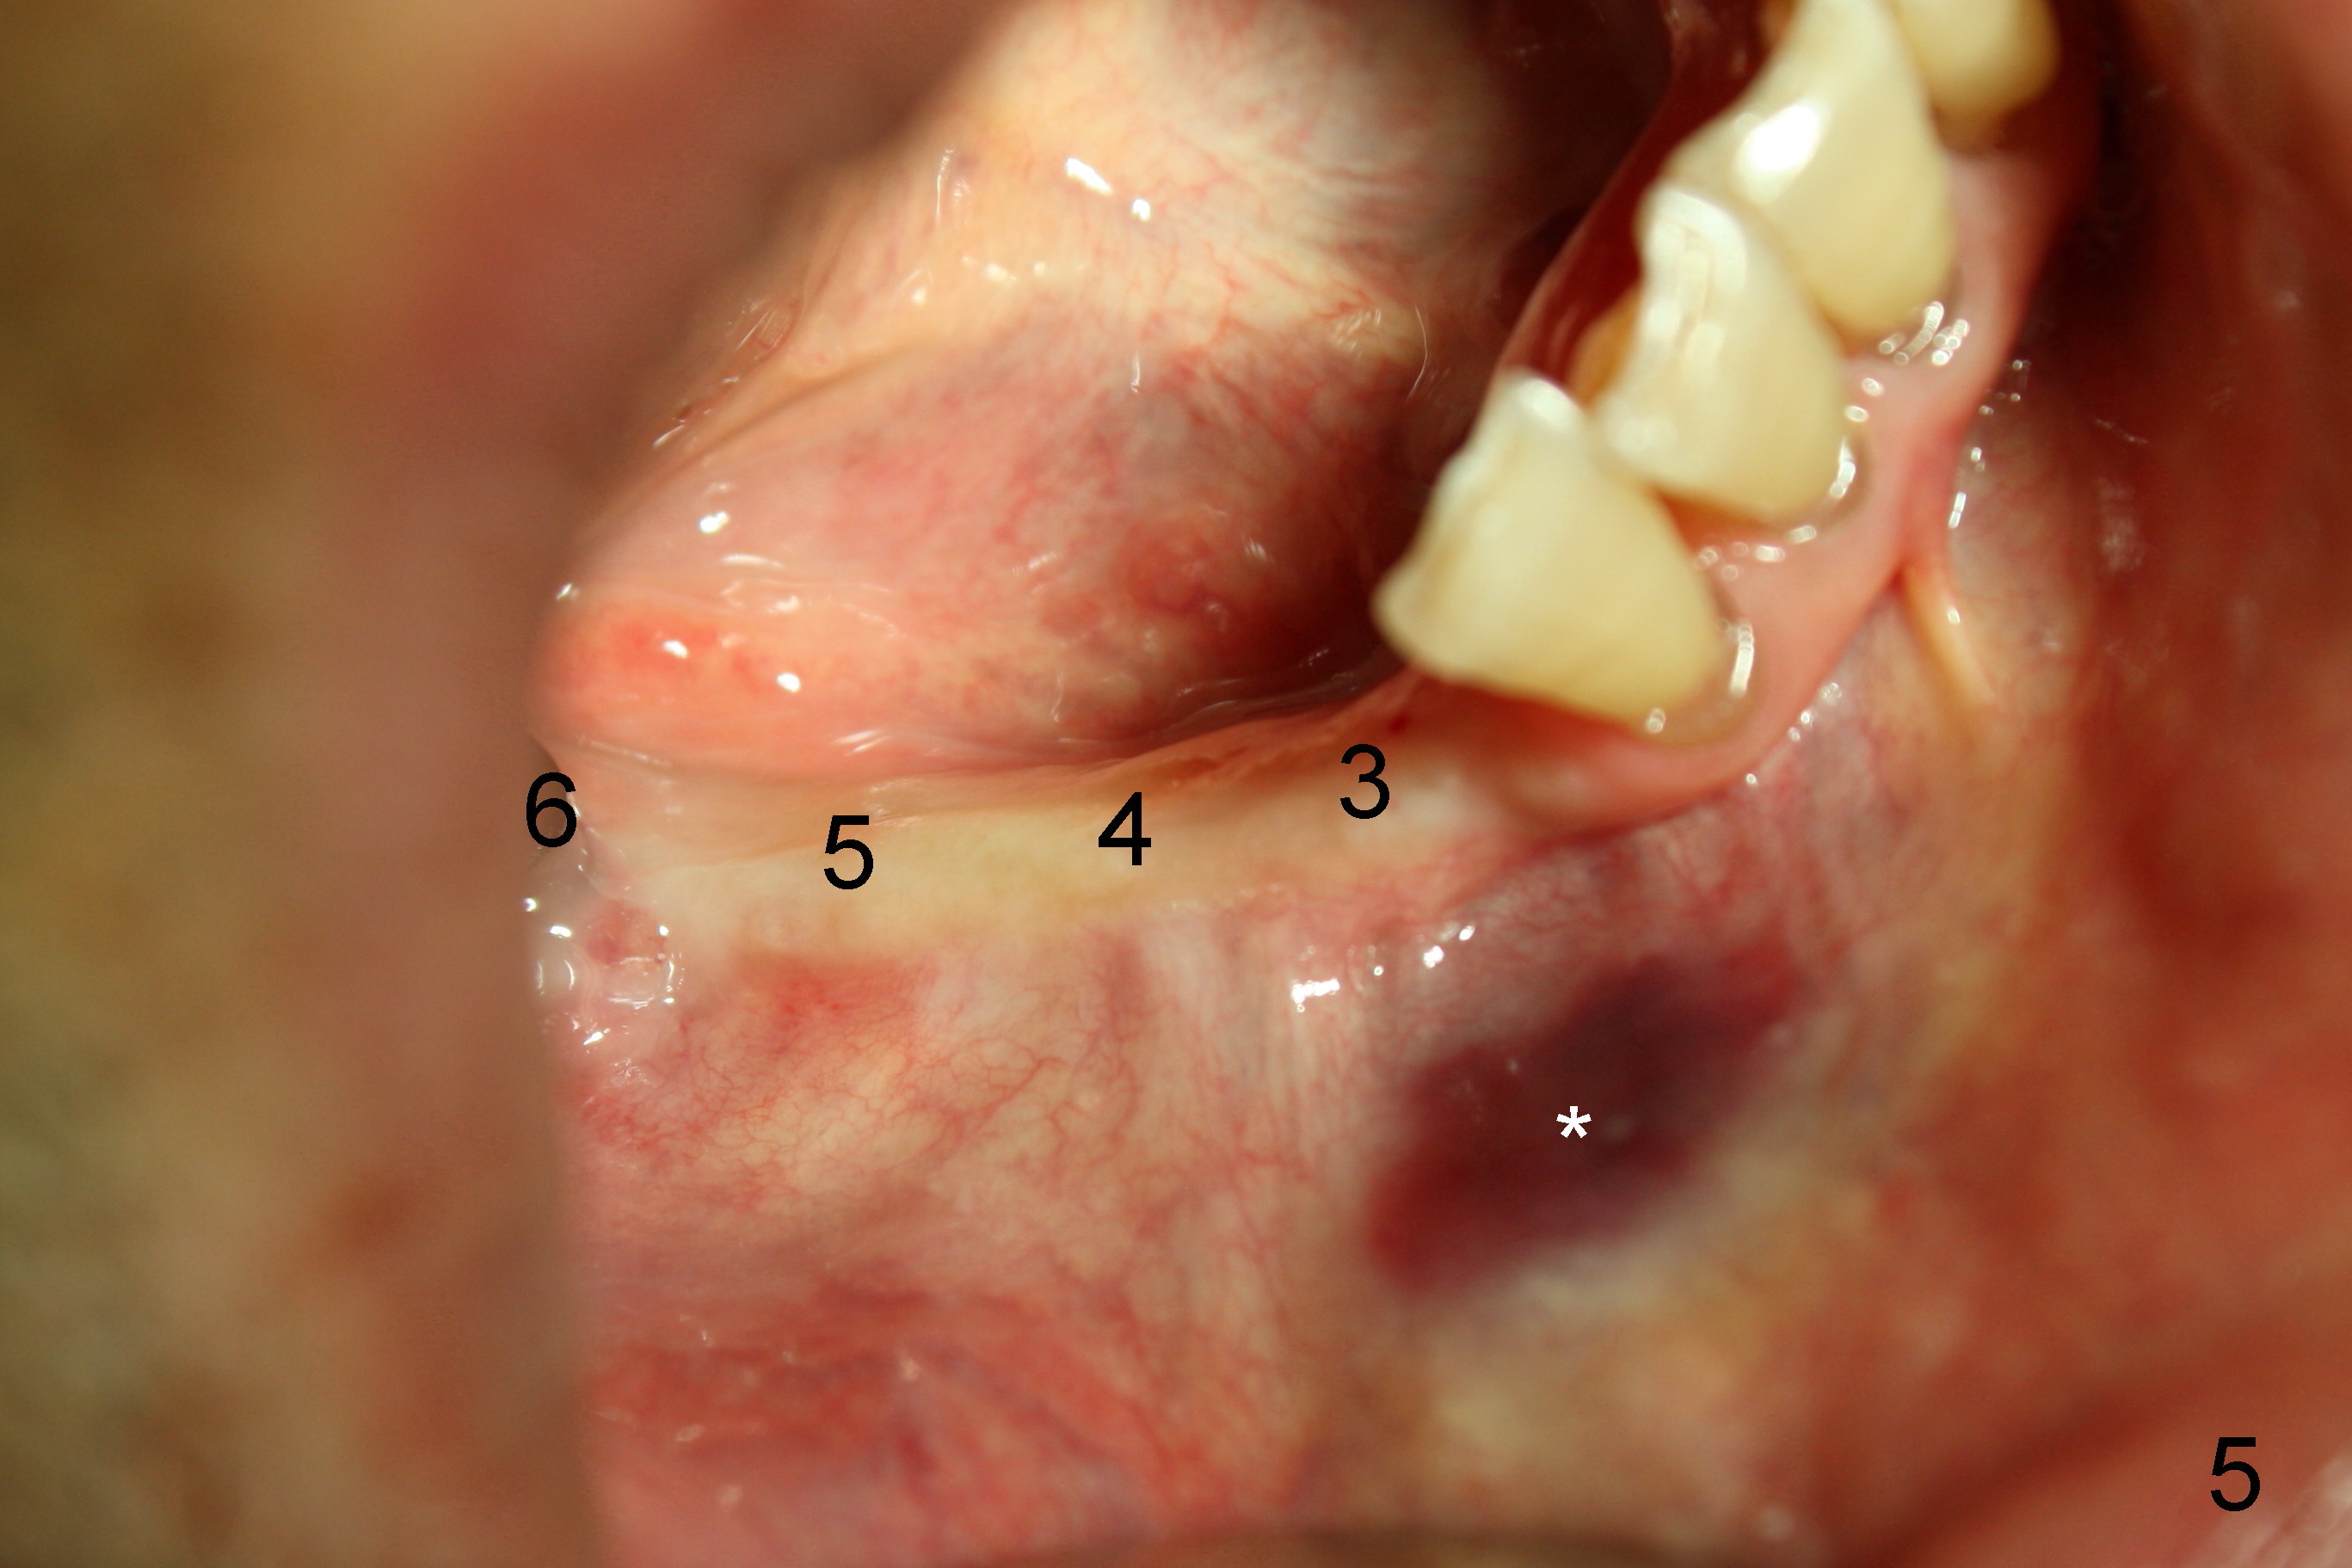

The lower right bridge (from canine (Fig.2: 3) to 1st molar (Fig.1: 6)) fails while a 77-year-old man is undergoing chemotherapy for urinary bladder cancer. The abutments of the bridge are extracted without plan for implants (Fig.4). Four months later, the patient returns for implants (Fig.3), but the ridge is narrow (Fig.5). While 2 of 3x14 mm 1-piece implant are placed at the canine and 1st bicuspid sites, 2 piece ones at the 2nd bicuspid and 1st molar sites (Fig.6: 3.5x11 mm, 5x14 mm). Soft (Fig.7-10) and hard (Fig.11) tissues heal 1 week (Fig.7) and 4 months (Fig.8-11). There is minimal bone resorption 1 year 7 months post cementation (Fig.12,13, non-splinting). It appears that narrow diameter implants are a valid solution to narrow ridge at the sites of the lower canine and premolar. As long as there are enough implants for function, the crowns are not necessary to be splinted. Surprisingly, the patient starts flossing after implant restoration. Retrospectively an immediate provisional bridge should have been fabricated.

There appears to be no bone loss 2 years 5 months post cementation (Fig.14). Gingival bands form around the implants at #27-29 three years 1 month post cementation (Fig.15 *).